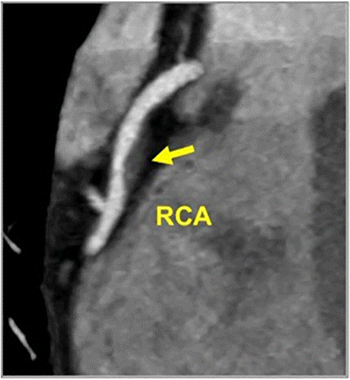

Emerging research revealed that a deep learning model had a nearly twofold increase in successful segmentation and reconstruction of coronary total occlusions (CTOs) on coronary computed tomography angiogram (CCTA) and a 73 percent reduction in post-processing and measurement time in comparison to a conventional manual approach.